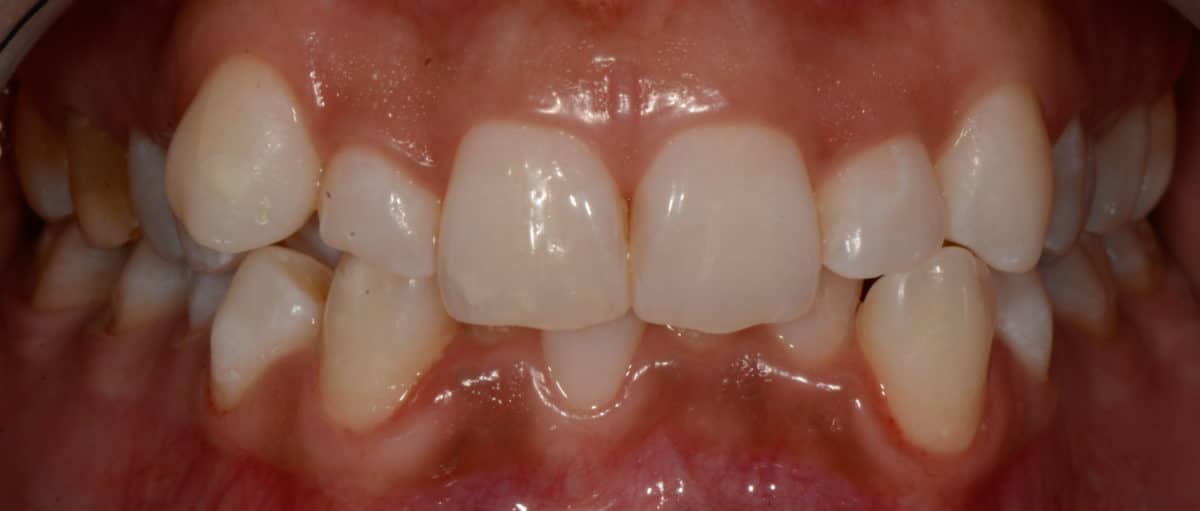

Cas #1 – Traitement avec des bagues, deuxièmes prémolaires et dent de sagesse supérieures ectopiques.